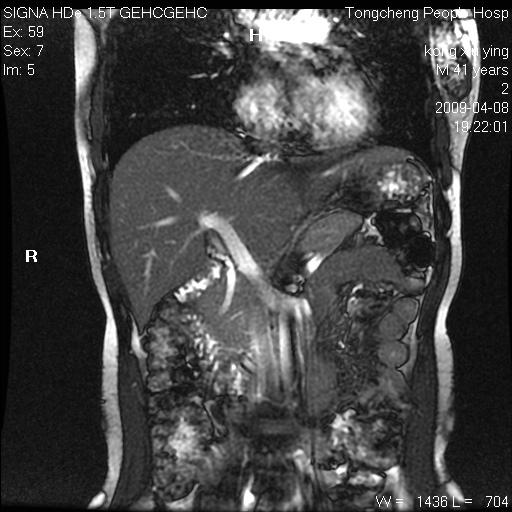

标题: CL1008:【经典】胆囊石榴籽样结石。

女,41岁。健康体检——彩超提示:胆囊显示不清。平素健康,无不适感。

腹部mr扫描及mrcp,图像如下: